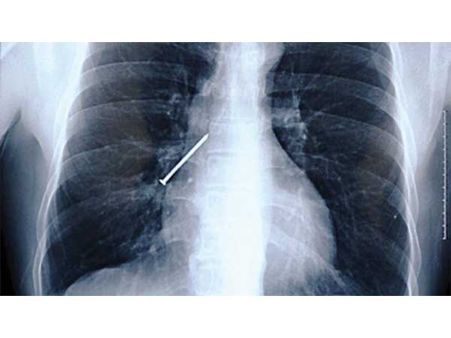

ખિલ્લી

ચીનના એક કાર્પેન્ટર દ્વારા ભૂલથી એક ખીલ્લી ગળાઇ ગઇ. તેના મોઢામાં ખીલ્લી હતી અને તેને ખાંસી આવી અને તે ગળાઇ ગઇ. એટલું જ નહીં આ ખિલ્લી તેના ફેંફસામાં અટકી ગઇ. જો કે ભારે મહેનત બાદ સર્જરીથી તેને દૂર કરવામાં આવી.